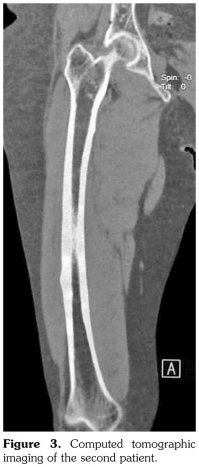

Case 2– A 61-year-old female patient presented with anterior thigh pain and difficulty in walking. Pain severity was 7 over 10 point according to visual analog scale. She had been treated with alendronate 70 mg per week with calcium plus vitamin D for two years. Plain radiographs of femur were taken upon clinical presentation. Cortical stress reaction was detected in both femoral shafts on plain radiographs (Figure 2). Computed tomographic imaging was performed to rule out fracture (Figure 3). Bone scintigraphy showed increased uptake in distal (1)/3 ends of femoral shafts (Figure 4). Serum calcium value was normal and urinary deoxypiridinoline level was mildly increased (46 nM/mMCre).

Bone scintigraphy of the patients revealed increased uptake in femoral diaphysis. Atypical bisphosphonate associated subtrochanteric and femoral shaft stress fractures show specific appearance on bone scintigraphy characterized by mild uptake in multifocal endosteal thickening of the lateral femoral diaphysis.(11)